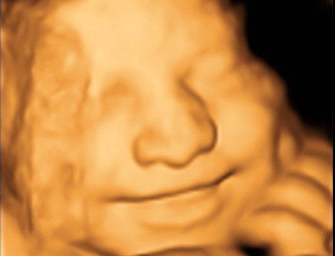

Dr. Sawant Diagnostic & Sonographic Centre - Image 1 Dr. Sawant Diagnostic & Sonographic Centre - Image 2 Dr. Sawant Diagnostic & Sonographic Centre - Image 3 Dr. Sawant Diagnostic & Sonographic Centre - Image 4